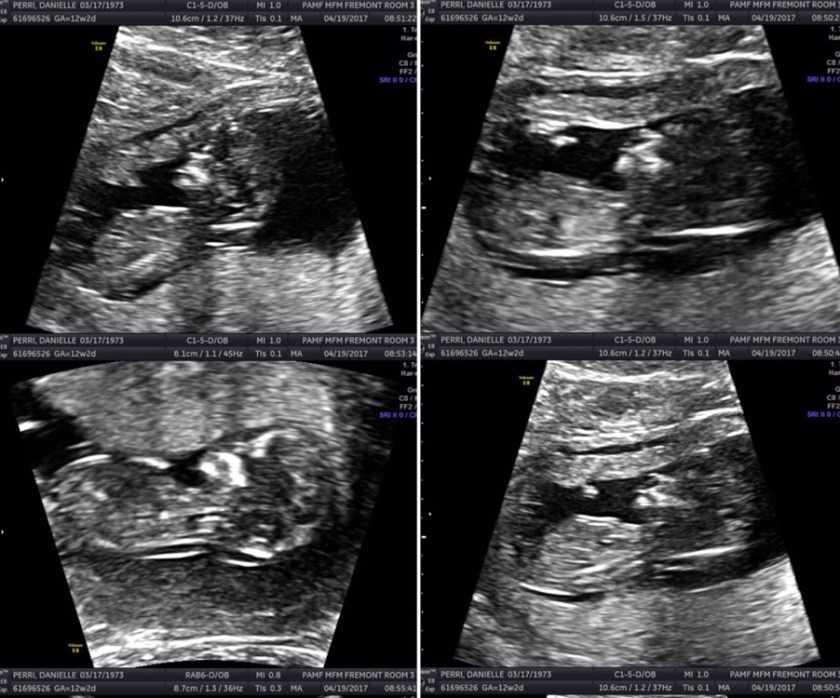

I had a blast taking so many pictures of my pregnancy and getting so many sonograms. In this one, he really looked so much like a baby and in many ways of the boy he turned out to be.